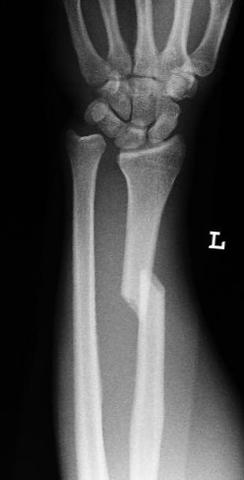

Arm Gebrochen, Wie Langer Dauert Der Heilungsprozess (Unfall, Heilung

gebrochen röntgenbild dauert heilungsprozess seesaw gutefrage heilung unfall dauer.